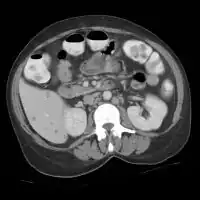

CT scan: Liver candidiasis - multiple small rounded foci in liver and spleen.